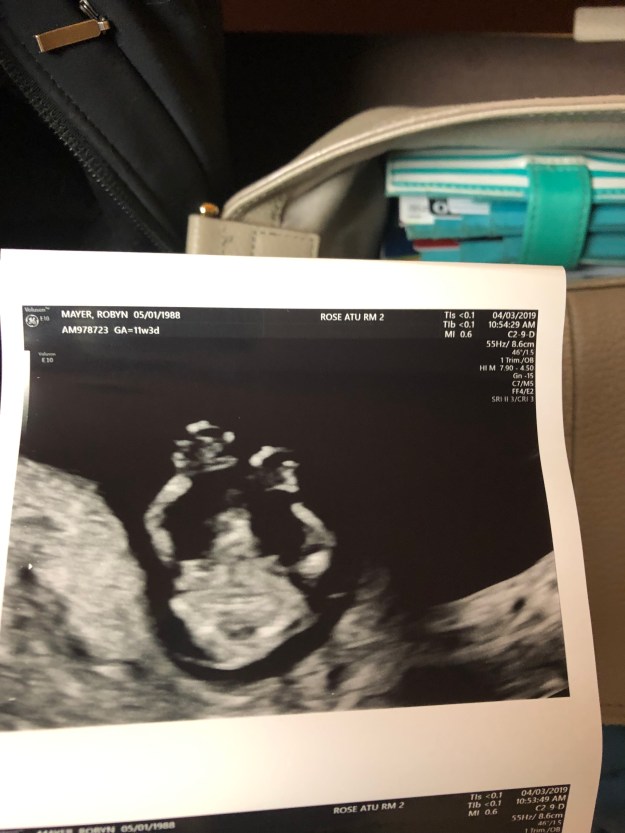

We first saw baby when they were a tiny blob attached to a yolk sack in week 8. By week 12, they looked a little more baby-like. My fondness for that little life grew exponentially watching them move around during that appointment, and I think that’s when it really hit me that that was MY baby growing.

Week #20 sonogram, in which a lil profile emerged!